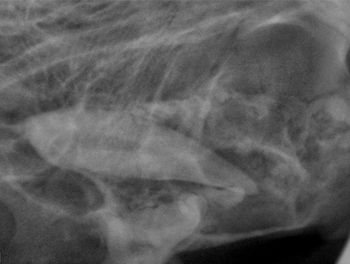

Two case examples display how radiography can reveal hidden pathology.

Correct management of periodontal patients in veterinary practice demands a thorough understanding of veterinary dental radiographic anatomy, periodontal probing and many times open evaluation and direct visualization of diseased areas. Stage III periodontal disease in particular requires advanced skills and familiarization with periodontal pathophysiology to make decisions to attempt to grow new supportive tissue adjacent to compromised teeth or extract them.